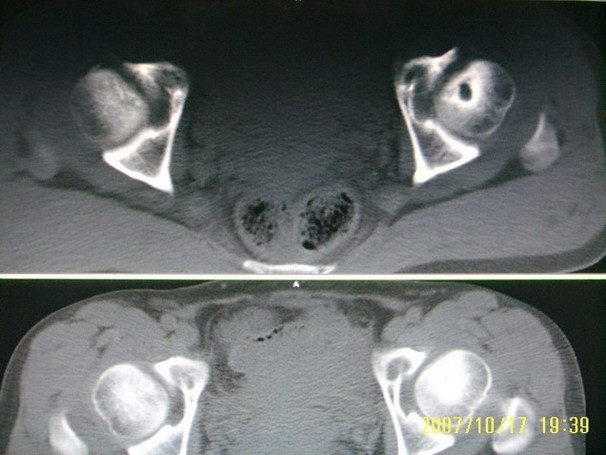

标题: CT10352:女,45岁,股骨头病变,如何诊断?

股骨头病变,如何诊断?

患者女,45岁,左髋部行走疼痛一年,无外伤史,无感染史。x片示囊状骨透亮区

左侧股骨头变形,密度增高,局部塌陷。多考虑:股骨头缺血性坏死伴退变!

左侧股骨头塌陷,其内囊变硬化,骨纹理改变考虑:左侧股骨头坏死及蜕变.